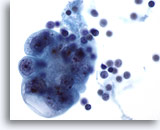

Peritoneal effusion: Metastatic carcinoma of the breast. Note cells with targetoid intracytoplasmic vacuoles containing mucin droplets. 40X

Metastatic carcinoma of the breast. Note cells with targetoid intracytoplasmic vacuoles containing mucin droplets.

40X